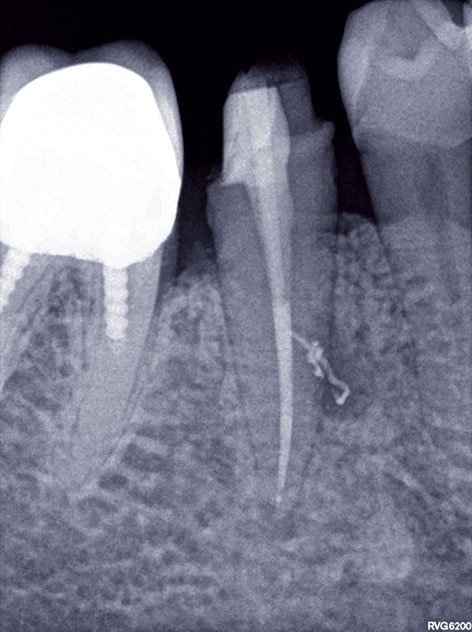

1. Une radiographie rétro-alvéolaire centrée sur 45 met en évidence une reprise de carie sous la restauration en composite et une lésion inflammatoire périradiculaire d’origine endodontique (LIPOE). Le test de vitalité est négatif.

3, 4, 5. La restauration est déposée, les tissus carieux éliminés et la cavité d’accès aménagée avant la réalisation du traitement endodontique. La radiographie postopératoire permet de visualiser l’obturation du canal latéral en regard de la LIPOE.